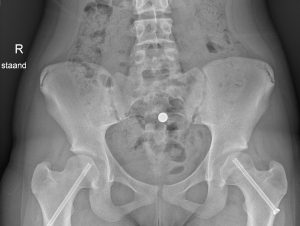

Epifysiolyse wordt behandeld door middel van een operatie. De kinderorthopeed zal met een schroef de heupkop weer op zijn plaats vastzetten. Dit moet meestal direct gebeuren om te voorkomen dat er groeiproblemen op de langere termijn ontstaan. Na de operatie leert het kind bewegen onder begeleiding van een fysiotherapeut. Zes weken na de operatie vindt er een controle plaats waarbij er een nieuwe röntgenfoto gemaakt wordt. Op onderstaande röntgenfoto zijn beide heupkoppen met schroeven vastgezet.

Epifysiolyse wordt behandeld door middel van een operatie. De kinderorthopeed zal met een schroef de heupkop weer op zijn plaats vastzetten. Dit moet meestal direct gebeuren om te voorkomen dat er groeiproblemen op de langere termijn ontstaan. Na de operatie leert het kind bewegen onder begeleiding van een fysiotherapeut. Zes weken na de operatie vindt er een controle plaats waarbij er een nieuwe röntgenfoto gemaakt wordt.